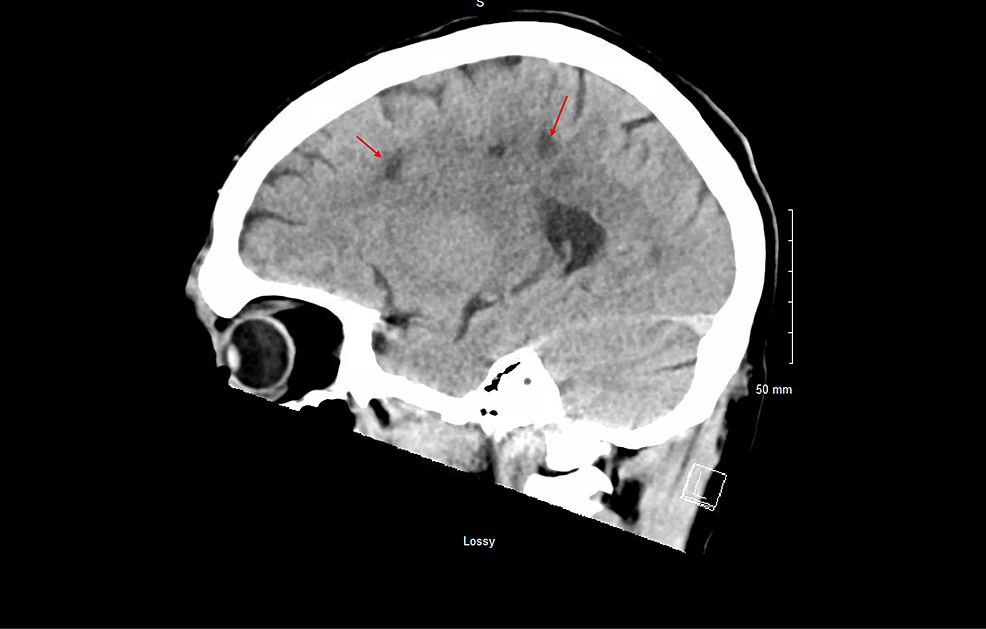

Repeat CT head, CTP of the head, and CTA of the head and neck revealed multiple white matter hypodensities concerning septic emboli, bilateral internal carotid artery 50% calcific stenosis, and no focal perfusion defects (Figure 2,3).

CT-head-axial-view-plain-revealed-multiple-white-matter-hypodensities-concerning-septic-emboli-(Red-arrows).

CT-head-sagittal-view-plain-revealed-multiple-white-matter-hypodensities-concerning-septic-emboli-(Red-arrows).